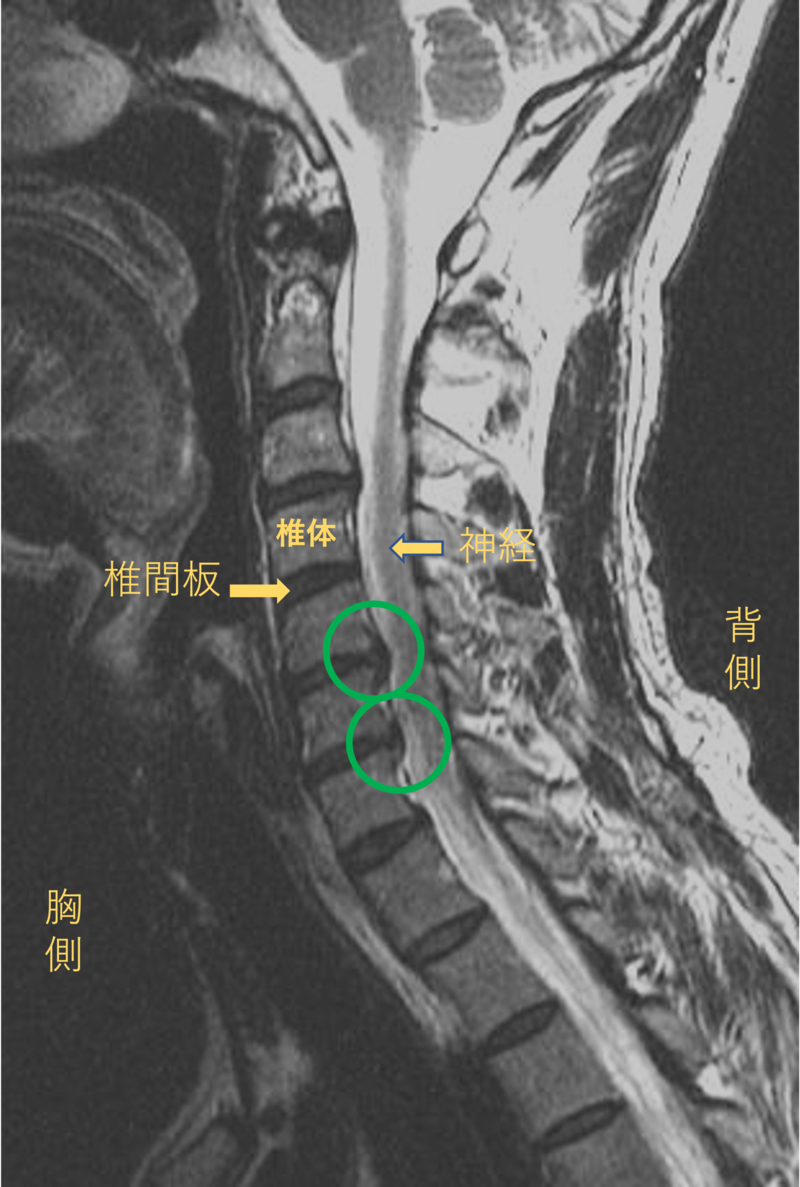

首を横から見たMRI画像です。

頚椎という骨と骨の間に椎間板と呼ばれるクッションがあります。

このクッションの中身が飛び出す状態が椎間板ヘルニアと呼ばれます。

このMRI画像では、椎間板が背中側に飛び出して神経が圧迫されることが痛み、しびれの原因となっておりました。